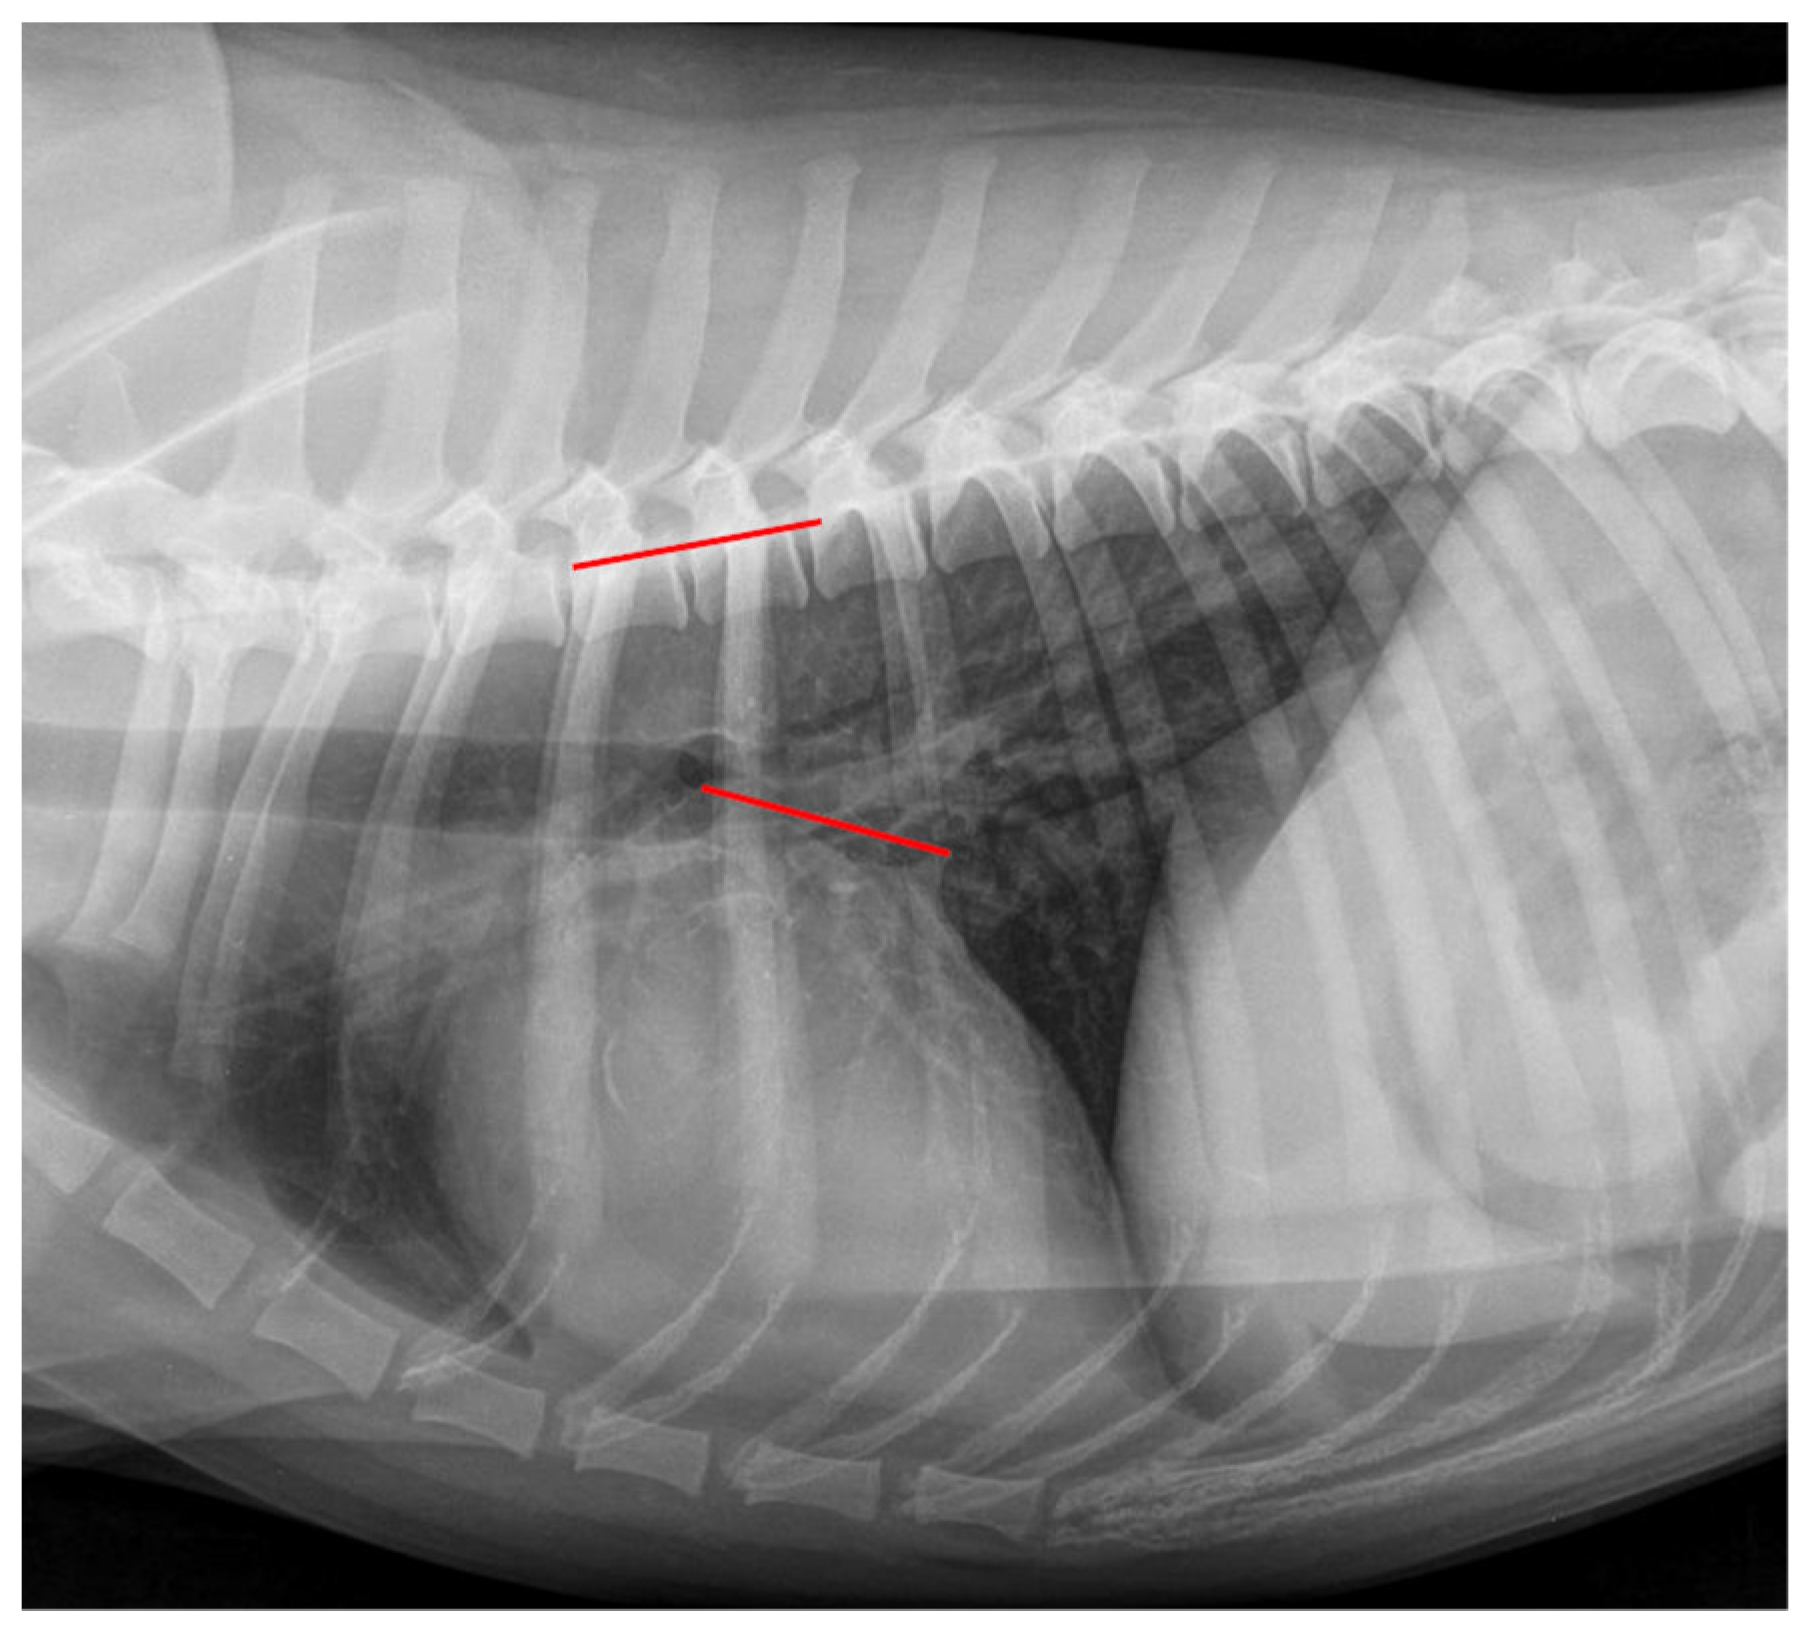

The VLAS was obtained as defined by Malcolm et al. (2018) [23], drawing a line from the ventral margin of the carina tracheae to the dorsal intersection between the cardiac silhouette and the caudal vena cava. Afterward, this line was transposed to the vertebral column and in vertebral units as described previously. A measurement example is displayed in Figure 4.

Figure 4.

Measurement example of VLAS. The Vertebral Left Atrial Size (VLAS) measurement in the same right lateral thoracic radiograph is shown in Figure 1. A line was drawn from the ventral margin of the carina tracheae to the dorsal intersection between the cardiac silhouette and the caudal vena cava (red line on cardiac silhouette). This line was transposed onto the vertebral column (red line on vertebral) as described in Figure 1. The VLAS was 2.2 vertebral units.